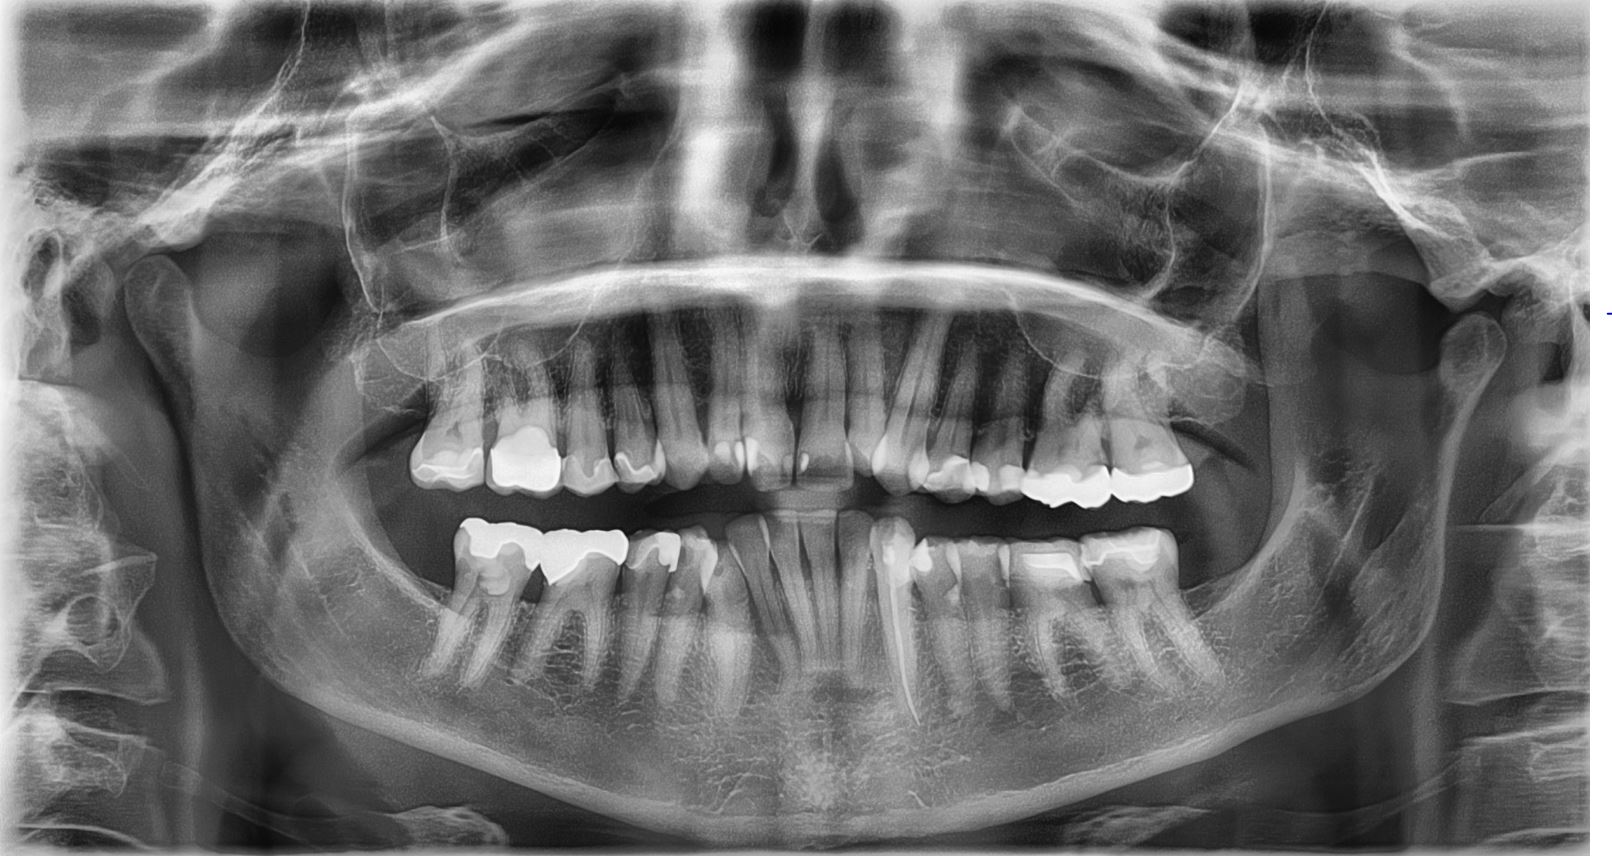

OPG(DENTAL X-RAY)

Orthopantogram and cephalogram is a kind of dental x-rays. An OPG produces wide views of the lower and upper jaws while a cephalogram is an x-ray of facial structures. A horizontal cephalogram produces a side profile picture of the face, jaws, and delicate tissue to evaluate the connection of the teeth to the jaws, the jaws to skull, and the connection of the delicate tissues to the teeth and jaws. A focused x-ray machine is used to generate the scans. During an OPG test, a part of the equipment will turn around the patient's head while they stay in one position either standing or sitting position.

WHY IS IT DONE?

Orthopantogram (OPG) is a close up image of the lower and upper jaws. The OPG provides information about the sensitive mouths. Doctors can also observe the infections, tumors, jaw joint defects, broken bones, etc with the help of OPG scan. It helps in the treatment of the teeth that includes dental implants, root canal treatment, crowns, and bridges. Child dentistry is also used OPG to observe the development of the new teeth under the baby teeth. It is a painless, quick and the patients are in contact with a minimal amount of low-level radiation.